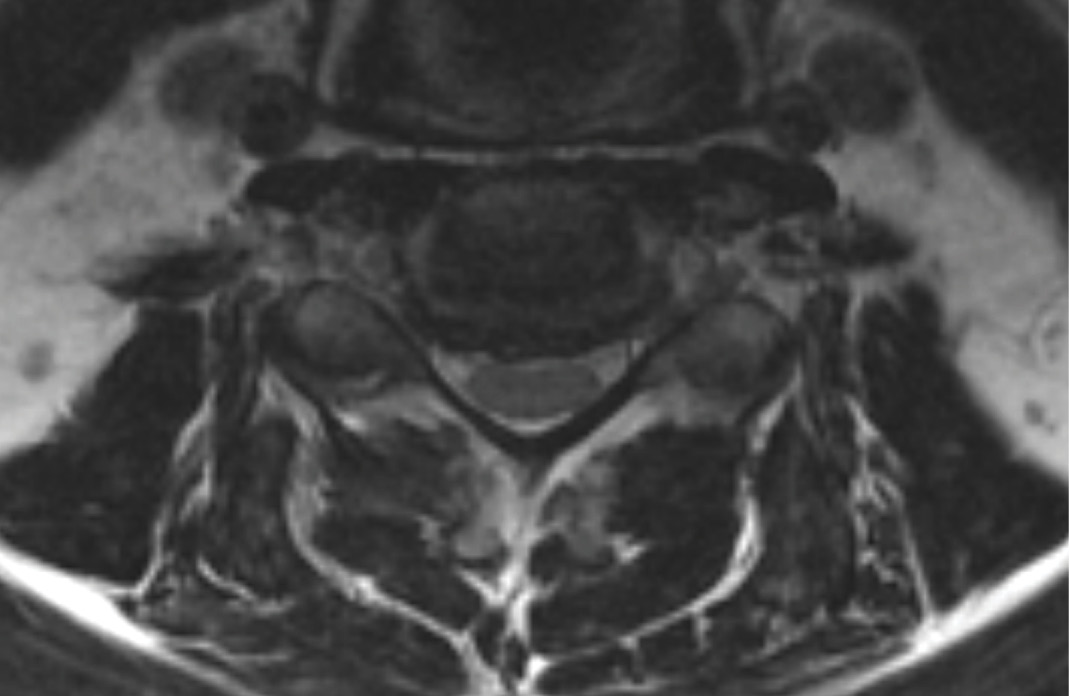

MRIs illustrated mild degenerative disc disease from C4-6 with disc herniations at both C4-5 and C5-6. The axial slice through C4-5 showed a right central disc herniation causing central and mainly right-sided foraminal stenosis. The axial slice through C5-6 showed a central disc herniation also causing central and mainly right-sided foraminal stenosis. The axial slice through C6-7 showed a left-sided disc herniation causing some left-sided foraminal stenosis, however, the patient did not demonstrate any left-sided symptoms.